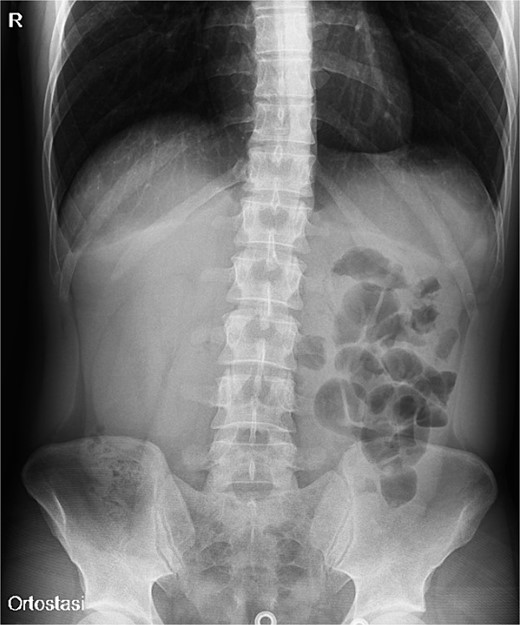

A 31-year-old male was complaining episodes of abdominal pain in the umbilical region with nausea. In medical history he underwent an appendectomy. Chronic gastritis was found on esophagogastroduodenoscopy (EGD) and proton-pump inhibitors (PPI) treatment was started, with regression of symptoms. After two months, he took ketoprofen for back pain for two days when a severe abdominal pain in the umbilical and right iliac region started, with nausea and vomit. He had normal vital signs and tenderness in the right lumbar and iliac regions. Blood exams showed leucocytosis (GB 14.120 × 106/ml) with neutrophilia (88%). A plain abdomen X-ray showed absence of representation in the right regions, with small bowel loops’ distension on the left (Fig. 1). An abdomen US displayed the presence of visceral distension with cockade appearance, consistent with an inflammatory condition of the cecum and the ileocecal site, with wall thickening of 6 up to 10 mm and free fluid near the cecum (Fig. 2). Contrast-enhanced CT confirmed wall thickening of the last ileal loop and the cecum up to 20 mm (Fig. 3A and B). Antibiotic therapy was started. The next day the pain worsened and there was an abdominal mass in the right iliac region with rebound tenderness. Blood examination showed further increase in leucocytosis (GB 18560) and a new CT was done. The wall thickening increased up to 24 mm, and the last ileal loop was more hypointense, with a twisted appearance around its mesentery (Fig. 3C). Exploratory laparotomy was performed. During surgery we found an ileal intussusception of the distal ileum near the cecum, and an ileocecal resection with ileo-colic anastomosis was done. On the first post-operatory day he developed haematochezia and acute anaemia, so he underwent reintervention with resection of the anastomosis and ileostomy. The following post-operative course was uneventful.

Abdomen ultrasound image displaying visceral distension with a cockade appearance consistent with an inflammatory condition of the cecum and the ileocecal site, showing wall thickening of 6 up to 10 mm and free fluid near the cecum.